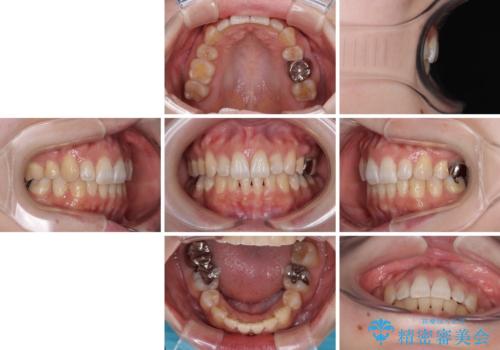

- 前歯のデコボコを気にして来院された患者様です。

非抜歯矯正にて治療を行うと、仕上がりで口元が突出する可能性があったため、小臼歯抜歯での矯正治療を行うこととしました。

上顎は左右の第一小臼歯2本を、下顎は左右の第二小臼歯2本を抜歯して、口元が突出しないようにしながら、奥歯の咬み合わせを改善していく治療計画としました。

目立たない装置が希望であったため、上顎が裏側装置である、ハーフリンガル装置を選択されました。

第二小臼歯抜歯としたため、治療期間は長くなりましたが、満足のいく仕上がりとなりました。